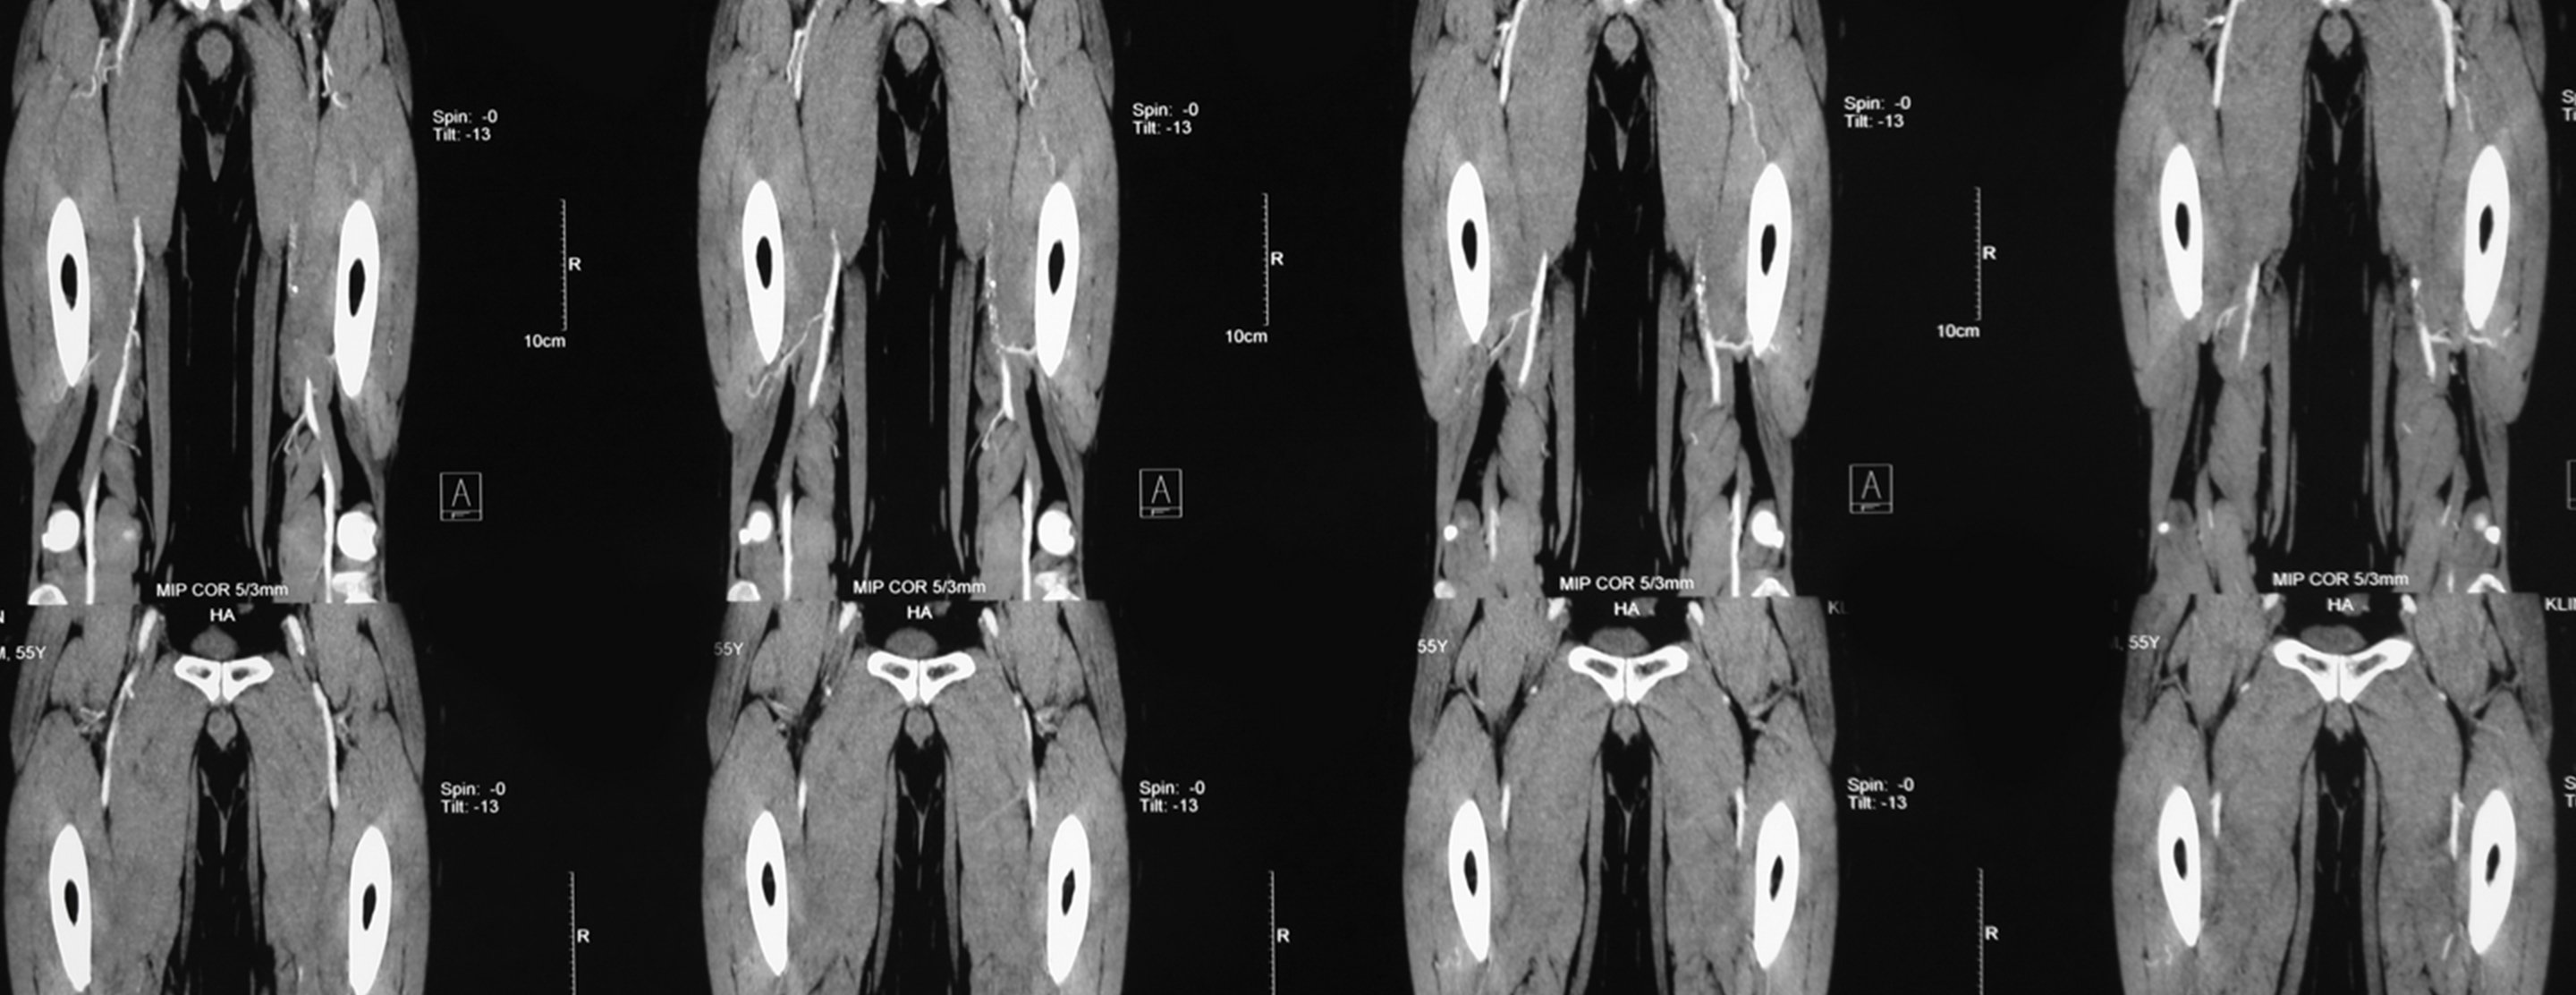

Extremity angiography

Extremity angiography is a test used to see the arteries in the hands, arms, feet, or legs. It is also called peripheral angiography.

- X-ray images of the arteries are taken.